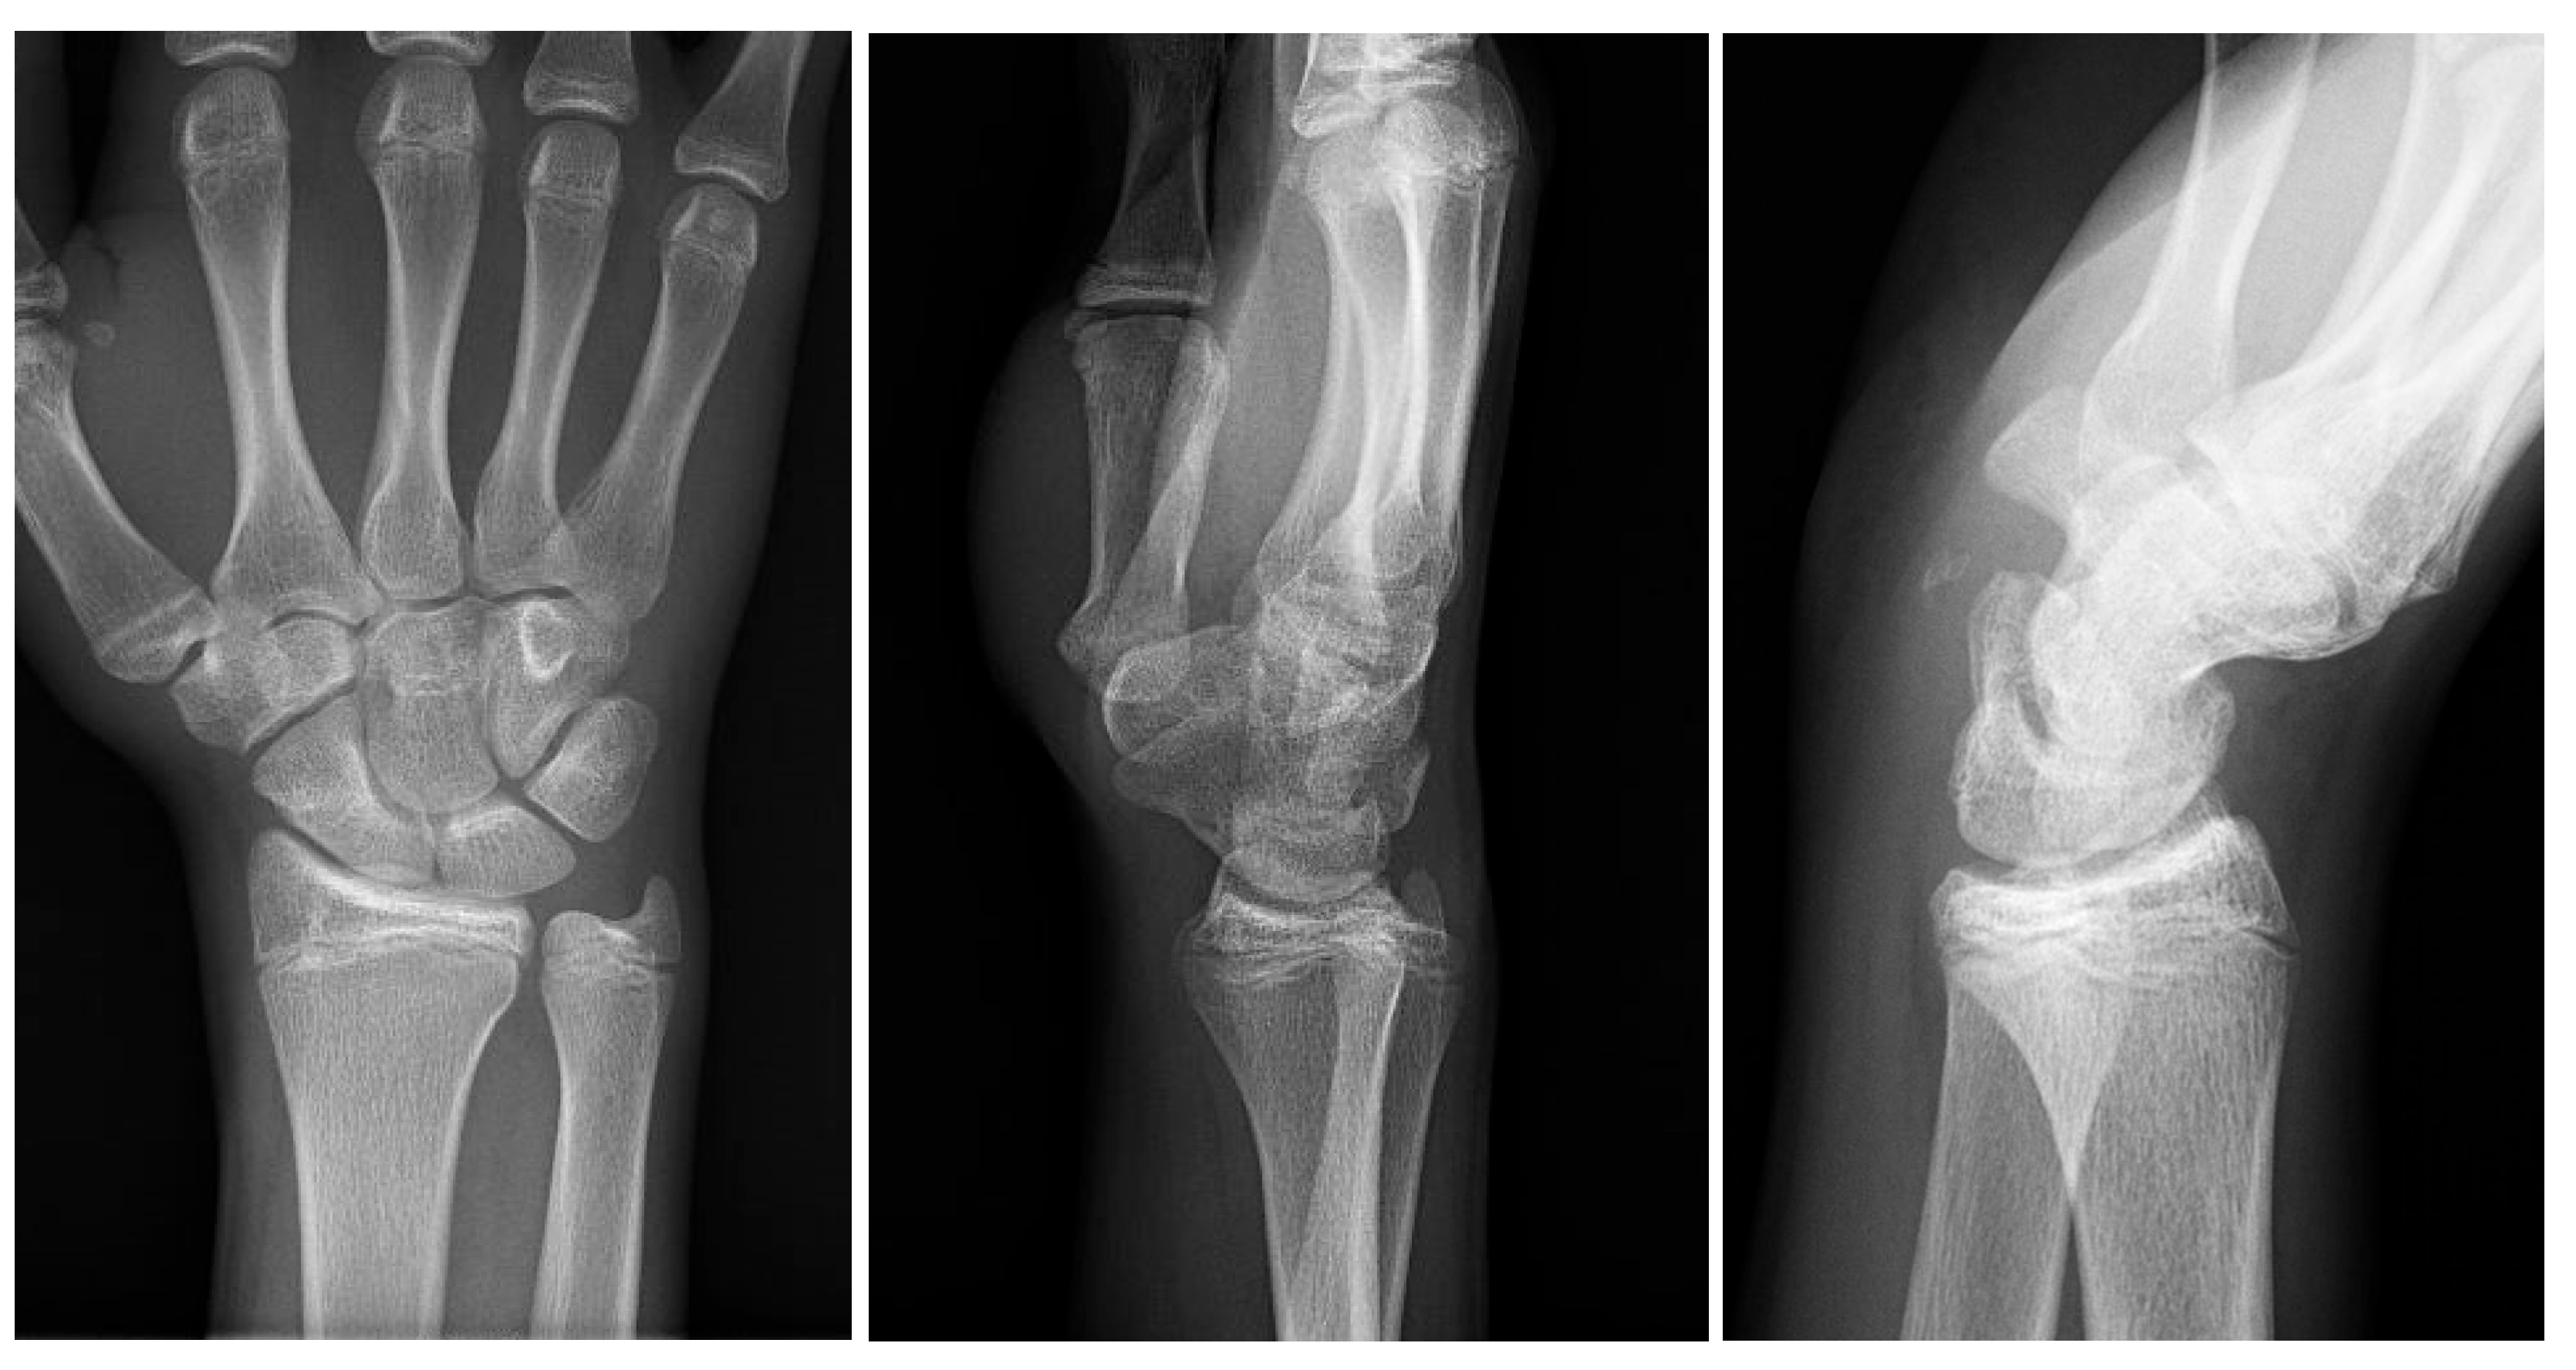

Initial conventional radiographic assessment showed no definitive fracture, with a potential suspicion of a proximal radius fracture (Figure 1). Due to significant tenderness over the radial fossa and pisiform, a CT scan was performed, confirming a nondisplaced scaphoid fracture and a suspected pisiform fracture with dislocation (Figure 2).

Figure 1.

Initial X-ray views in ap (left) and lateral (right) planes.